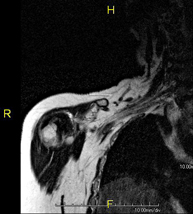

- Shoulder MRI

Examination to study injuries to tendons, muscles and joints. Its main use is to diagnose injuries to the rotator cuff tendons. It lasts approximately 20 minutes. It is a radiation-free procedure.